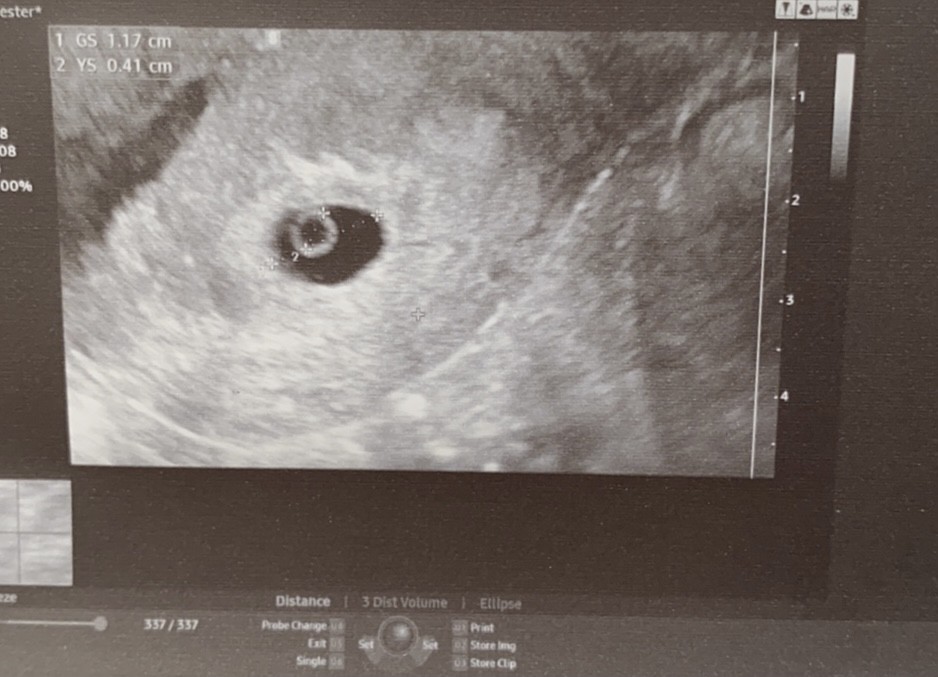

A wizyta super ! Wszytsko jest jak najbardziej okey:) nawet słyszałam mega słabe bicie serduszka ale to jeszcze za wcześnie ;) wstawiam zdjęcie :)

• AFCF6FB8-B298-4AF1-B185-ABBA15FE7BD8.jpeg

AFCF6FB8-B298-4AF1-B185-ABBA15FE7BD8.jpeg

118,2 KB · Wyświetleń: 115